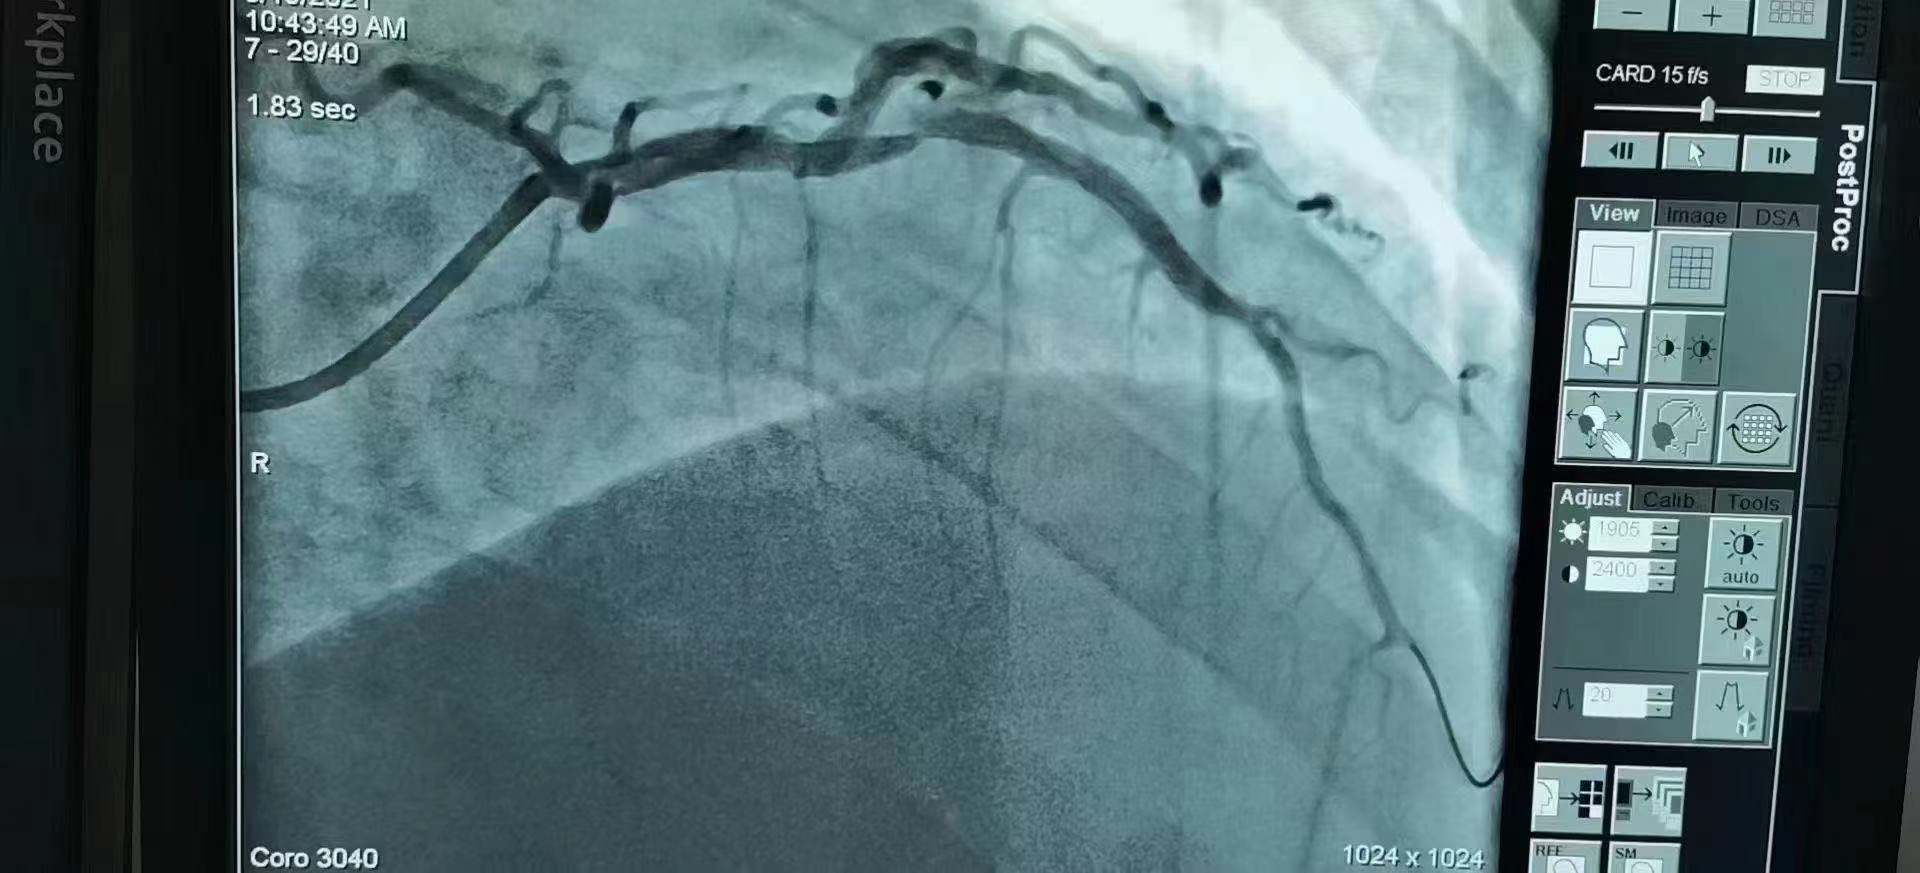

青島市第三人民醫院 李曉主任團隊成功為患者植入Xinsorb生物可吸收支架!

祝賀 青島市第三人民醫院  李曉主任團隊成功為患者植入Xinsorb生物可吸收支架!